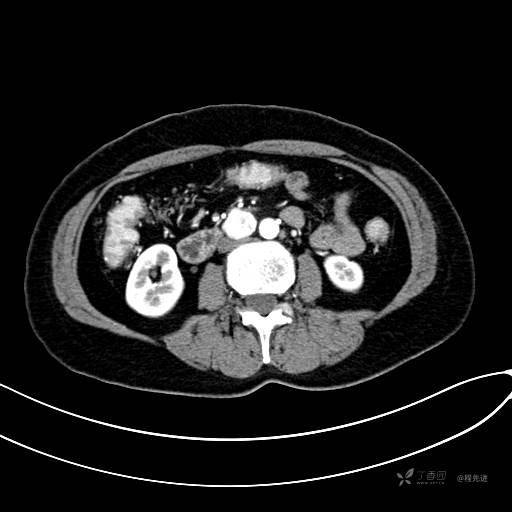

CT增强动脉期